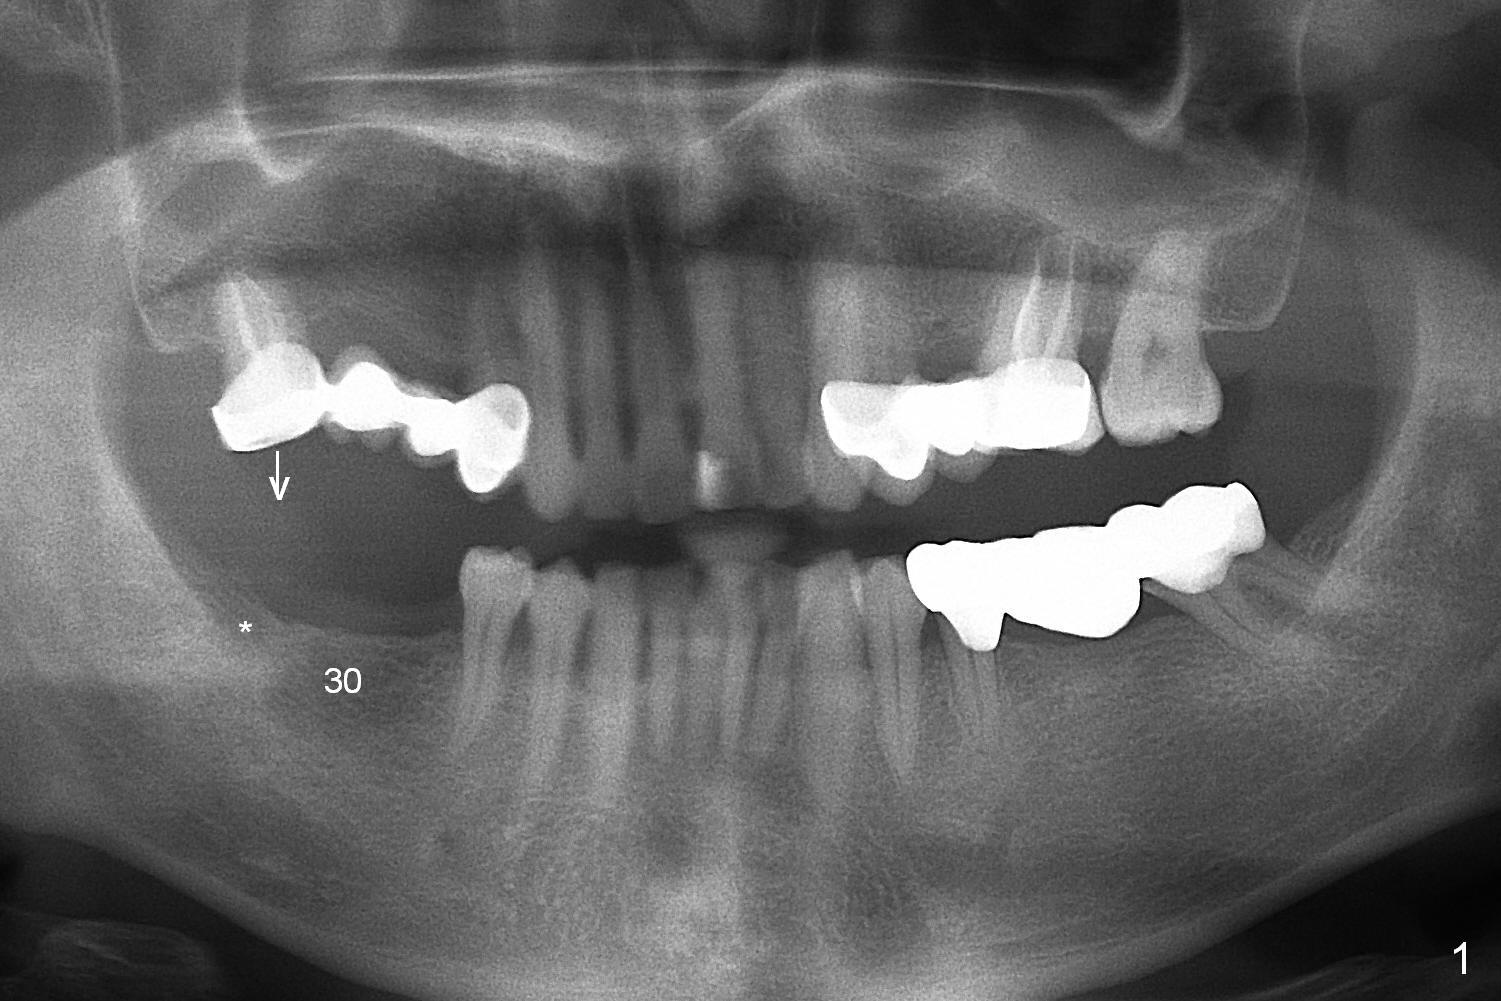

The bone height is good (Fig.2 (red dashed line: the superior border of the Inferior Alveolar Canal)).  Implants at #30 and 31 are expected 5x12 or 14 and 5x10 or 12 mm, respectively.  The abutments are 6.8x4(2) and 6.8x4(1) mm.